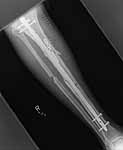

Hello Bill,

THX for the good source. We use an "alternative" technique - a small wire distractor which allows to avoid this problem rather easily (image attached). And i guess it could help in the case but the patient is far from here.

![]() |